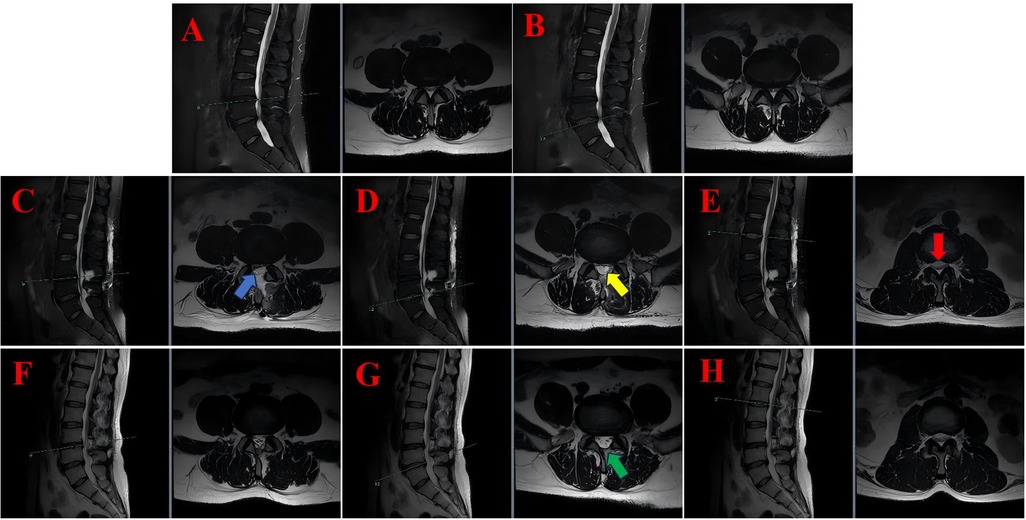

Background: Biportal Endoscopic Spinal Surgery (BESS) is a minimally invasive technique that has gained popularity for performing spinal procedures, including discectomy, decompression, and interbody fusion, in the cervical, thoracic, and lumbar regions. Whilst dural tears, epidural haematoma and transient paresthesia are well-documented complications associated with BESS, cases of subdural hygroma remain exceedingly rare. The present study presents a case series of three patients who developed postoperative subdural hygroma following BESS. An accompanying literature review was conducted in order to explore potential mechanisms and management strategies. Case Presentation:The initial case pertained to a 35-year-old male patient who underwent a cervical discectomy and foraminal decompression via BESS for the treatment of cervical spondylosis. Subsequently, the patient developed a cranial subdural hygroma. The second patient, a 53-year-old male, underwent a lumbar discectomy and decompression via BESS for lumbar disc herniation with concomitant spinal stenosis. Postoperative imaging revealed extensive lumbar subdural hygroma. The third case report concerns a 74-year-old male patient who underwent BESS decompression surgery for lumbar spinal stenosis. Postoperatively, the patient developed a subdural hygroma in the lower lumbar region. Conclusion: The development of subdural hygroma following BESS may be attributed to a combination of factors, including occult dural tears, abrupt alterations in intraspinal pressure, and ischemia-reperfusion injury. In view of the potential clinical implications of this rare complication, greater awareness and monitoring is warranted in the postoperative management of patients undergoing BESS.